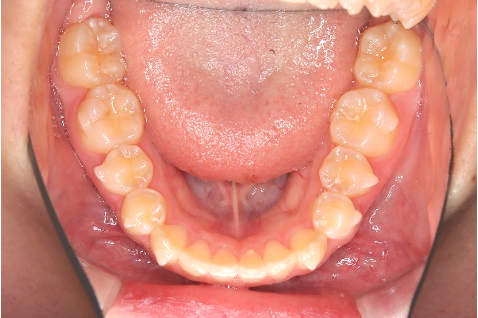

【10代女性】前歯のがたつきを治したい・見た目をきれいにしたい

「前歯のがたつきを治したい・見た目をきれいにしたい」とのことでインビザライン矯正をご希望の患者さんでした。歯並びもキレイになりお喜びいただけておりました。

術後

性別:女性 / 年齢:10代

| 主訴 | 前歯のがたつきを治したい、見た目をきれいにしたい |

| 期間 | 15ヶ月 |

| 費用 | 385,000円 (デンタルローン 3,800円/月) |

| 治療内容 | 治療プラン)ライトパッケージ 治療枚数)28枚 |

| 治療に伴うリスク | 矯正終了後は、リテーナーを指示通りに使用し、歯の後戻りを防ぐ必要があります。 |